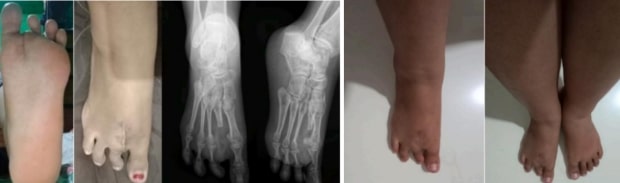

Publikasi ilmiah Dr. dr. Yuni Artha Prabowo P, Sp.O.T.Subsp.Onk.Ort.R(K), ini berjudul Clinical diagnosis and management strategies for Macrodystrophia Lipomatosa: Insights from a rare case report yang dipublikasikan pada International Journal of Surgery Case Reports Volume 134, September 2025. Kasus yang diangkat berasal dari seorang perempuan berusia 31 tahun yang mengalami pembesaran progresif pada jari kaki kedua sejak usia dua tahun. Kondisi ini tidak hanya menimbulkan perubahan bentuk fisik, tetapi juga menyebabkan nyeri kronis dan gangguan fungsi berjalan yang signifikan selama bertahun-tahun.

Melalui pemeriksaan radiologi, ditemukan adanya tonjolan tulang (exostosis) disertai pembengkakan jaringan lunak. Hasil biopsi kemudian mengonfirmasi diagnosis MDL, sebuah kelainan pertumbuhan langka yang ditandai dengan proliferasi berlebihan jaringan lemak. Setelah melewati evaluasi menyeluruh, tim medis memutuskan melakukan tindakan second ray amputation atau amputasi pada jari kaki kedua sebagai solusi terbaik untuk mengurangi beban mekanis, menghilangkan nyeri, dan mengembalikan mobilitas pasien.

Hasil operasi memberikan dampak yang sangat positif. Pasien kini dapat beraktivitas dengan lebih leluasa tanpa rasa sakit yang sebelumnya mengganggu. Keberhasilan penanganan ini menjadi bukti penting bahwa kombinasi diagnosis dini, evaluasi komprehensif, serta intervensi medis yang tepat mampu meningkatkan kualitas hidup penderita penyakit langka.